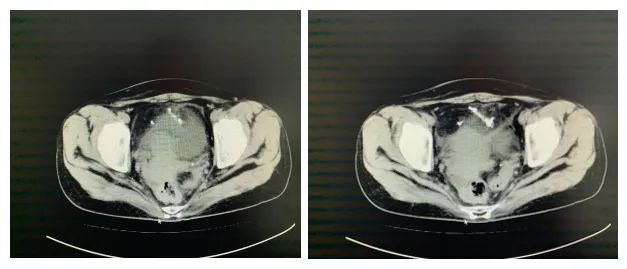

患者姜某,女,39岁,体检发现血尿10余天,追查原因,行CT检查后回报盆腔金属高密度影,部分位于膀胱腔内。

患者10年前曾于当地二人麻将 行节育器置入术,但之后仍有3次怀孕,分别行引产,患者曾有疑问,未予重视。根据患者入院相关化验检查,初步诊断为盆腔异物(节育环可能),考虑到患者已出现血尿症状,且异物长时间停留在腹腔可能出现穿孔、粘连、损伤肠管等诸多问题,在耐心的与患者及其家属沟通病情、消除紧张情绪后,最终对此患者行手术治疗。